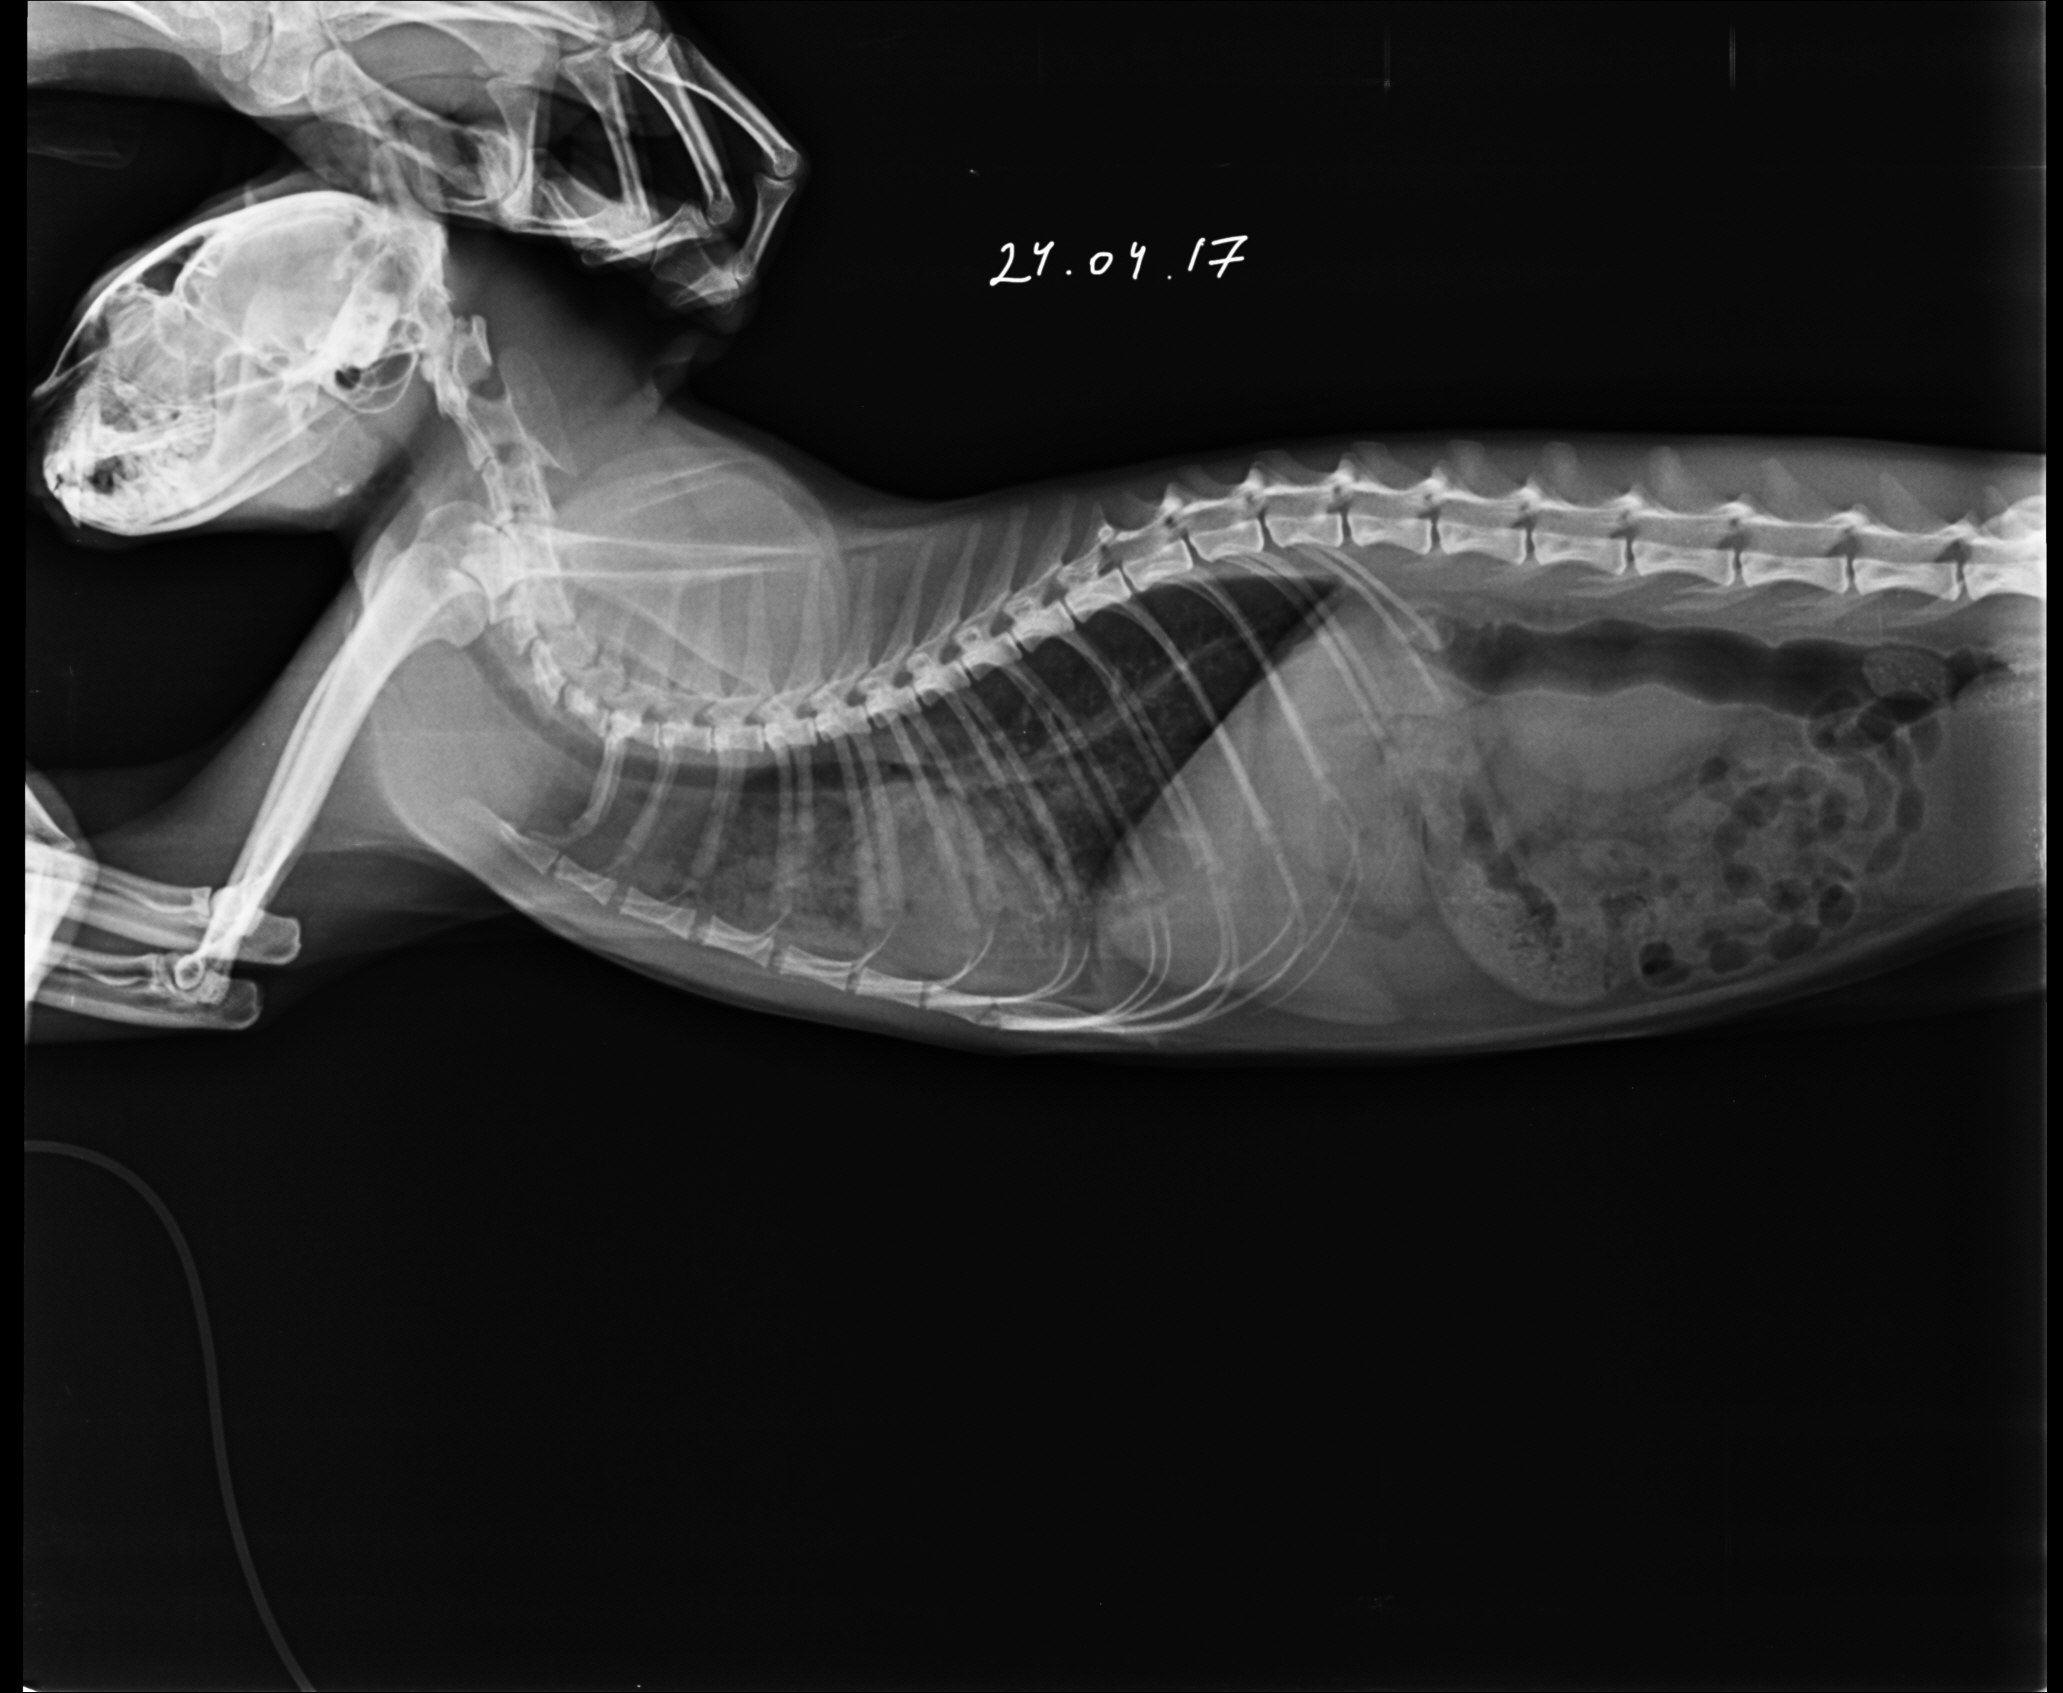

В клинике собаке сделают рентген, который подтвердит или опровергнет отек легких, а также проведут осмотр собаки, прослушают ее и выполнят ряд лабораторных исследований.

Для диагностики отека легких у собак используются такие методы, как аускультация, рентгенография грудной клетки или ультразвуковое исследование, также требуется анализ крови. Электрокардиограмма, анализ мочи и измерение кровяного давления — другие важные тесты, позволяющие выяснить, есть ли у вашей собаки отек легких.

Если состояние вашего питомца стабильное, можно выполнить рентгенографию грудной клетки, положив собаку на спину. На этой рентгенограмме могут быть признаки отека легких, такие как повышенная интерстициальная или альвеолярная непрозрачность. У собак, страдающих кардиогенным отеком легких, также могут наблюдаться кардиомегалия и расширенные легочные вены.

Рентгеновские снимки являются основным инструментом для диагностики отека легких, поскольку они выявляют жидкость внутри легких собаки. Рентген также может выявить увеличенное сердце или другие аномалии сердечной мышцы.